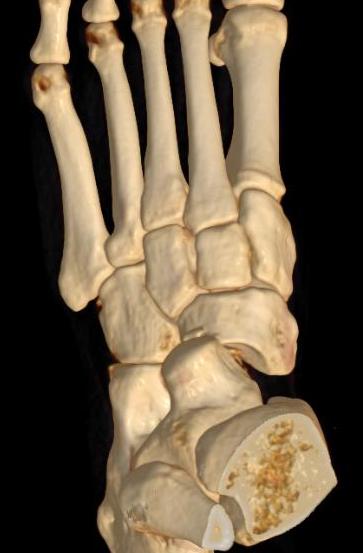

Chopart joints

- talonavicular joint

- calcaneocuboid joint

Ligamentous +/- fracture dislocations

Fractures - trans-navicular / trans-cuboid